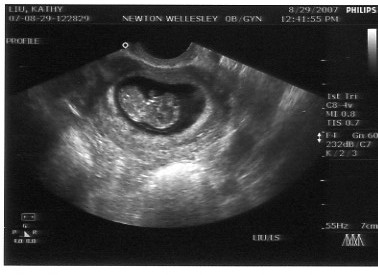

Kathy got an appointment right away to get an ultrasound to judge how far along the baby already was. It

turns out we were 9 weeks along (the fetus was about 3 cm long). When Jon saw the pictures, he began

referring to the baby as his "beanie baby" since it looked like a bean to him.